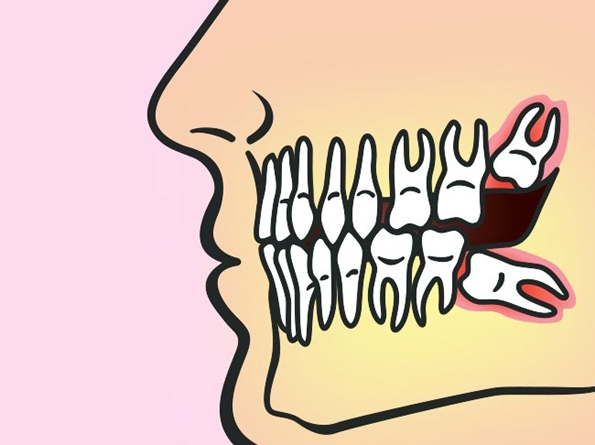

Нема ништо лошо во тоа да ги оставите умниците доколку редовно одите на заболекар и правите рендгенски снимки. Само така ќе можете навреме да откриете ако има некаков проблем (како на пример неправилно растење на умниците) и да направите операција за да ги отстраните. Докторите препорачуваат да го направите ова што е можно побрзо бидејќи откако ќе наполните 25 години, сите коскени ткива се конечно формирани и забите потешко се отстрануваат, а ткивата побавно заздравуваат.